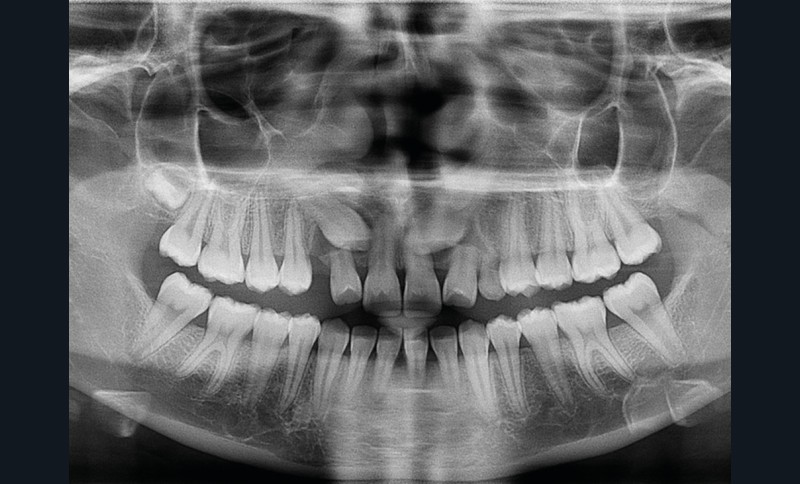

Les examens cliniques et radiologiques ont mis en évidence l’inclusion de 13 et 23, une légère classe II bilatérale par perte d’ancrage, un biotype parodontal de type IV de Maynard et Wilson avec une insertion du frein mandibulaire antérieur papillaire, une biproalvéolie et une typologie hypodivergente. La réalisation d’un examen tridimensionnel a permis de confirmer la localisation palatine de 23 et vestibulaire de 13 ainsi que de visualiser l’étendue des résorptions radiculaires touchant 12, 21 et 22 (fig. 1a-i).

Le plan de traitement choisi comprend les extractions de 63, 12, 22, 34 et 44. Ce choix s’est porté d’une part sur le fait de la présence de résorptions très avancées de 12 et 22 et d’autre part sur la correction de la biproalvéolie facilitée par l’extraction de 34 et 44 qui ont par ailleurs un diamètre légèrement inférieur à 35 et 45.

La décision d’extraire des incisives latérales maxillaires doit être mûrement réfléchie et expliquée clairement au patient ; des échecs dans la mise en place des canines incluses pouvant survenir [1]. D’après Kau, la mise en place de 13 et de 23 était dans ce cas difficile avec des scores respectifs de 15 et 18 [2]. Une décharge ainsi qu’un consentement éclairé spécifique ont donc été signés par les parents avant le début du traitement.

Les résorptions radiculaires des dents adjacentes aux canines maxillaires incluses sont en effet fréquentes avec un risque plus important chez les femmes. La localisation sagittale de la canine incluse constitue un facteur de risque dans la présence de résorptions radiculaires [3]. Le recours aux examens tridimensionnels est donc indispensable dans le traitement de ces cas.